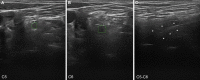

Results: Fifteen adult VEGBS patients were identified with a mean age of 57.8 years. At first NCS, VEGBS sub-typing was only possible in 3 (20%) cases that showed an axonal pattern, the remaining patterns being mixed (combining axonal and demyelinating features) in 6 (40%), equivocal in 5 (33.3%), and normal in 1 (6.7%). Upon serial NCS, 7 (46.7%) cases were categorized as acute demyelinating polyneuropathy, 7 (46.7%) as axonal GBS, and 1 (6.6%) as unclassified syndrome. Antiganglioside reactivity was detected in 5 out of the 7 axonal cases. Nerve US showed that lesions mainly involved the ventral rami of scanned cervical nerves.

Conclusions: Serial electrophysiological evaluation is necessary for accurate VEGBS subtype classification. Ultrasonography helps delineate the topography of nerve changes.